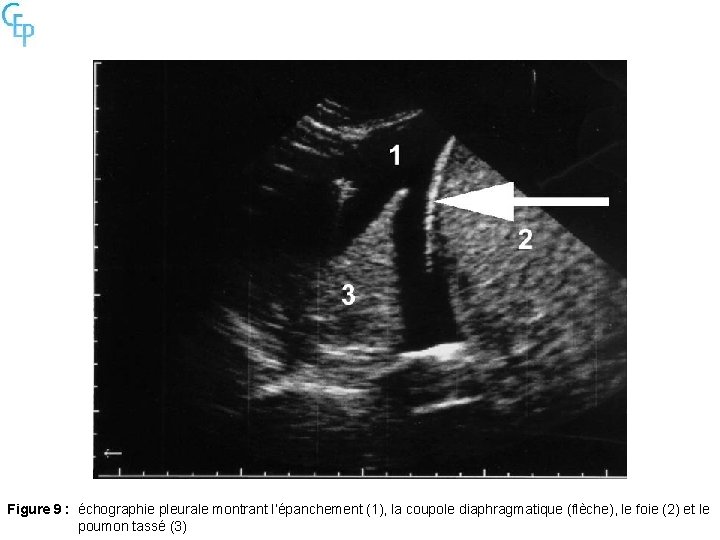

Figure 9 : échographie pleurale montrant l’épanchement (1), la coupole diaphragmatique (flèche), le foie (2) et le poumon tassé (3)